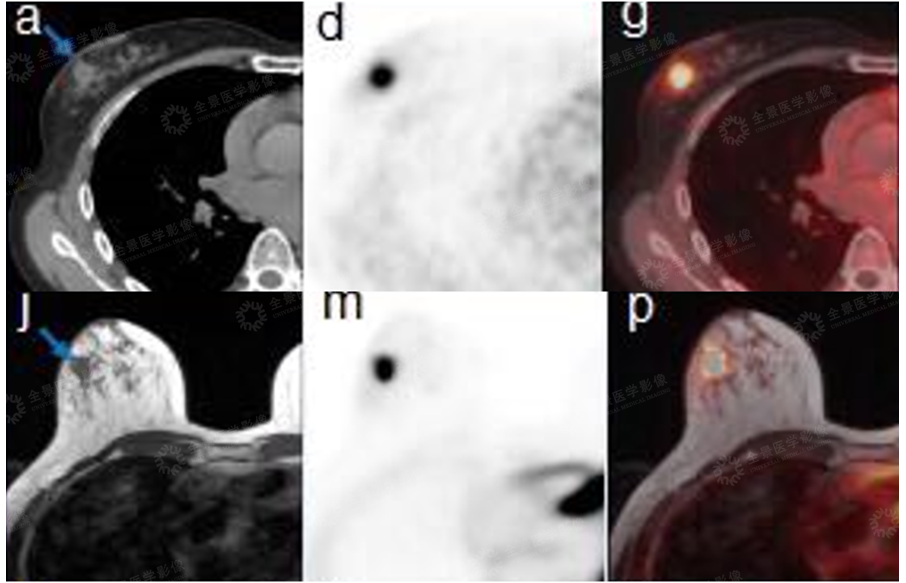

乳腺

案例:中年女性无明显不适,体检发现右侧乳腺小结节,性质不明。后为明确诊断,行PET/CT-MR异机融合检查。

表现:右乳外上象限软组织信号小结节,边界清楚,FDG局限性摄取增高。综合考虑为早期乳腺癌。

病理:漫润性乳腺癌。

肺部

案例:中年男性,左肺上叶后段结节状高信号影,FDG局限性摄取增高。

病理:腺癌。